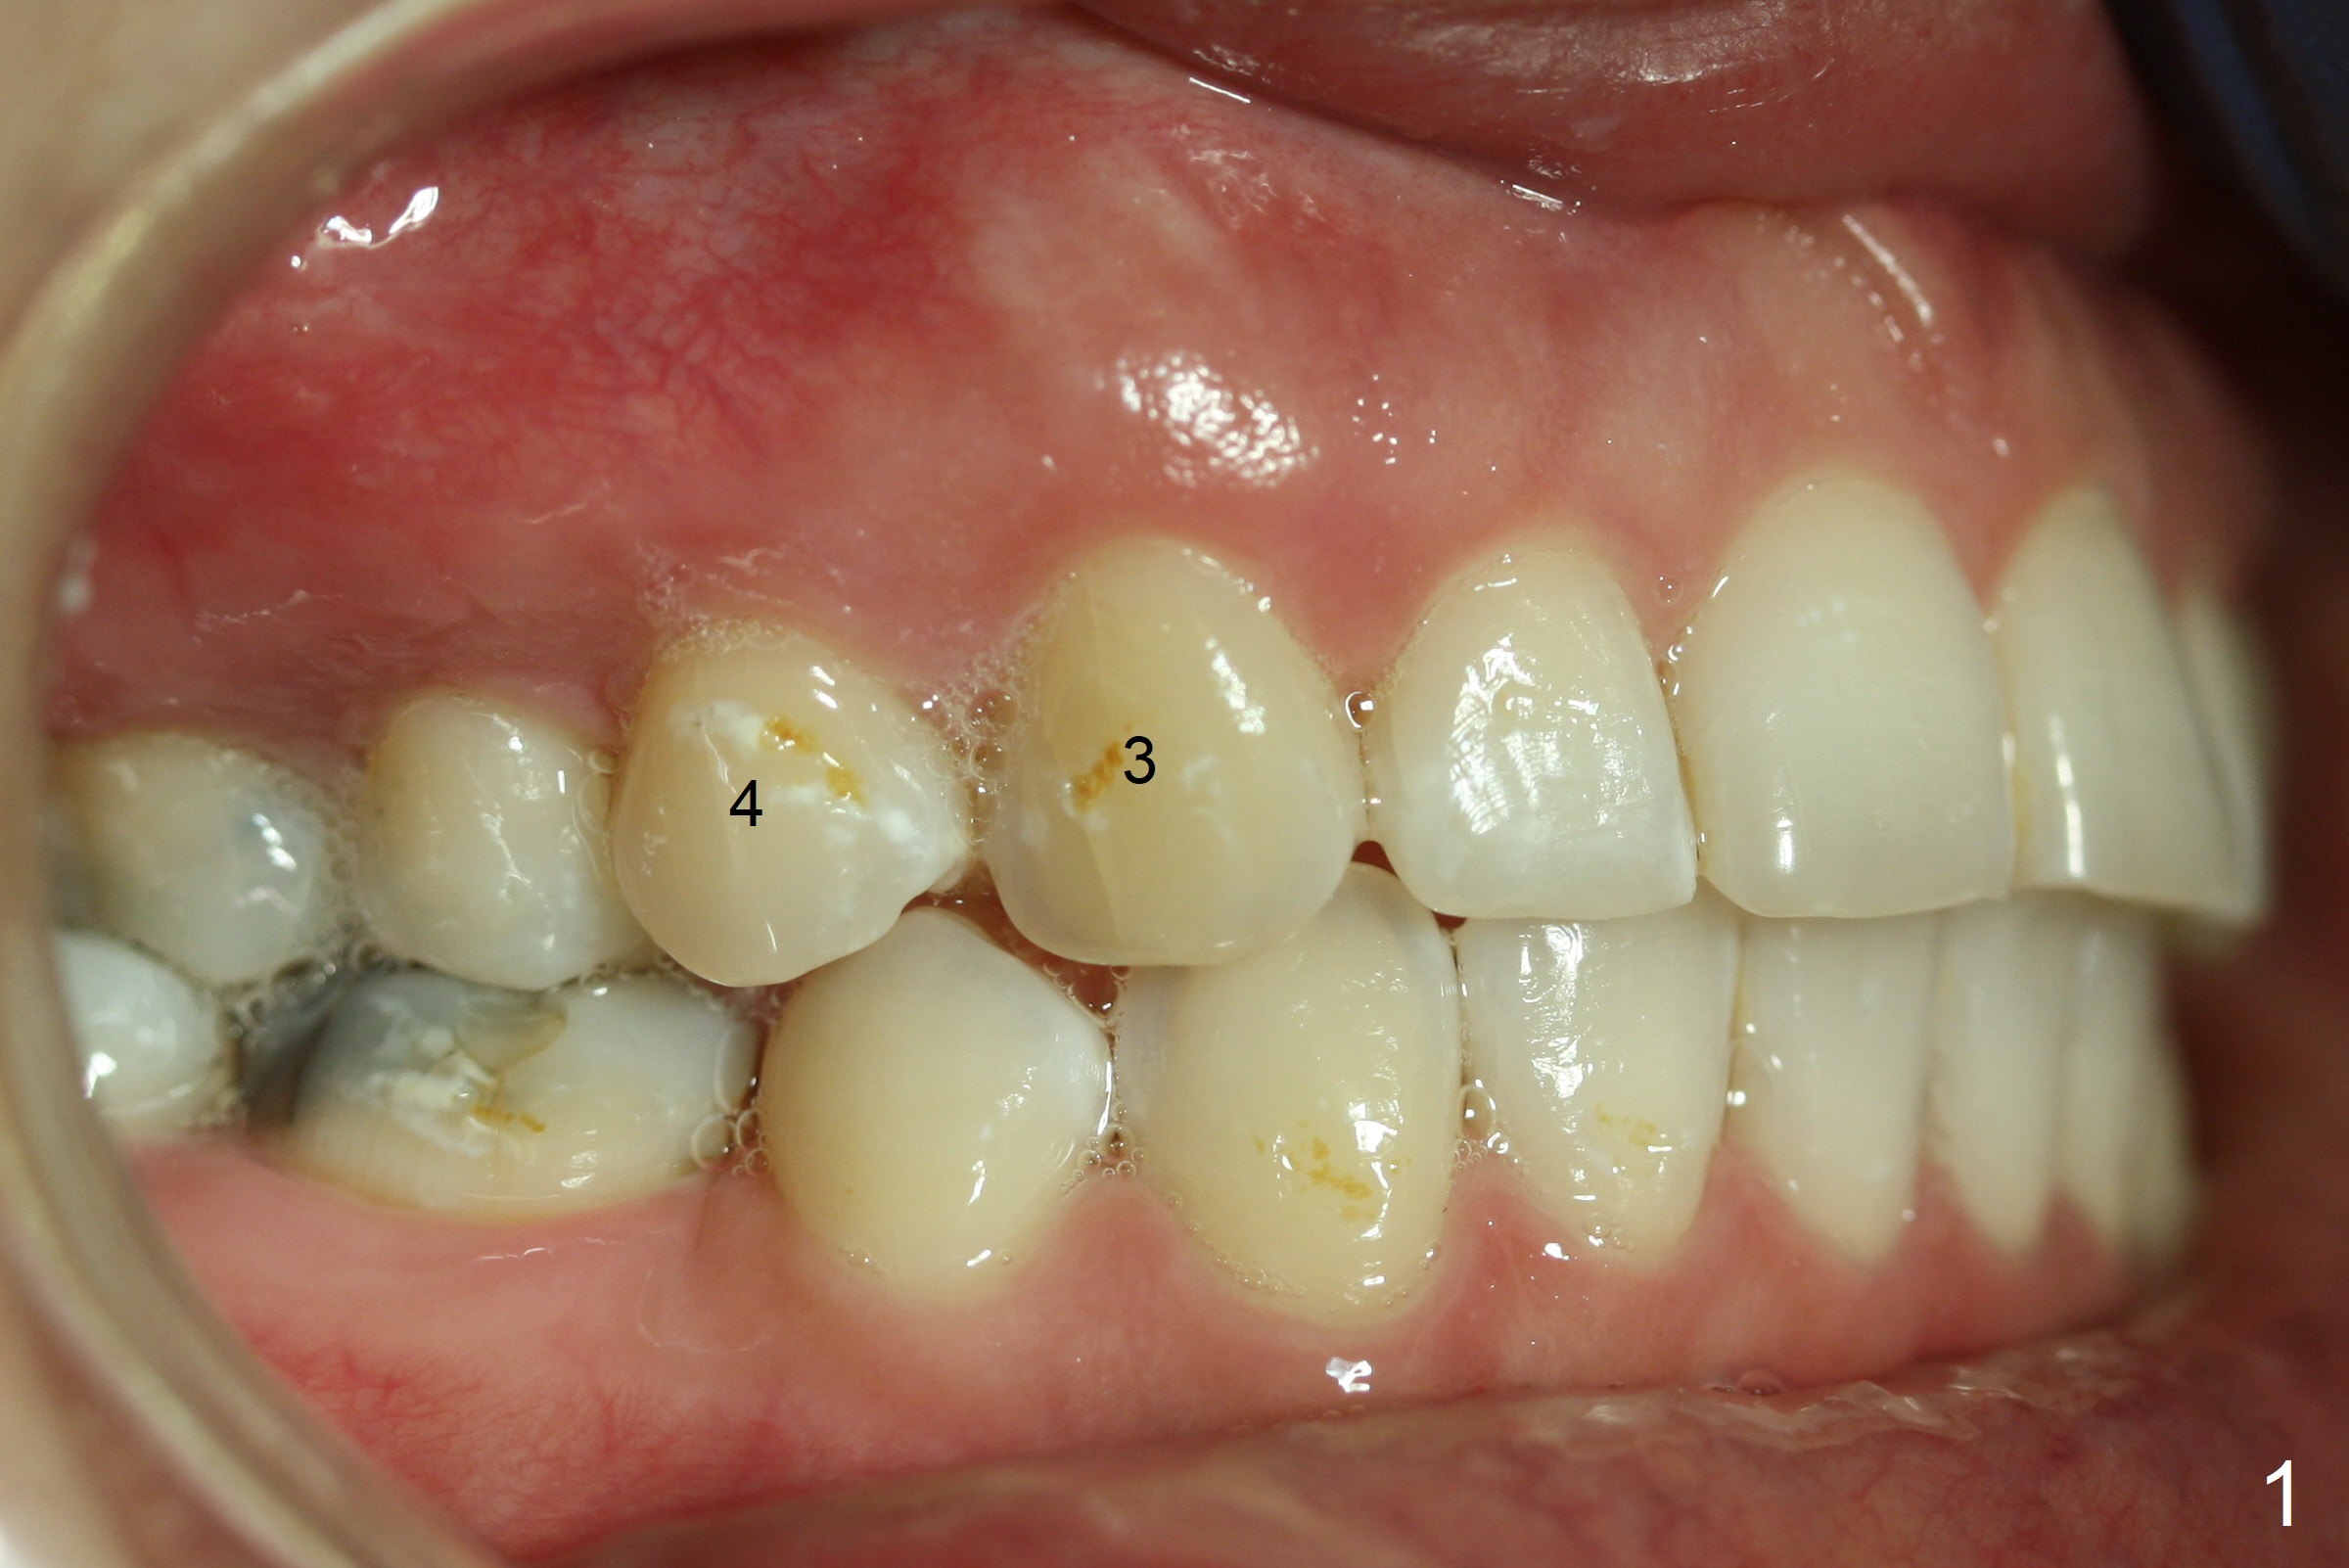

Discoloration of Upper Canines and

1st Bicuspids

Five months post debanding, the upper right canine becomes transiently symptomatic (tender to touch). Although both the right (Fig.1) and left (Fig.2) canines (3) and 1st bicuspids (4) discolor, the right ones are necrotic (pulpal test). It appears that these two teeth have periapical radiolucency (Fig.3,4), while the lateral incisor has shortened root (2). The longest tooth (upper canine) appears to be the most vulnerable to trauma associated with orthodontic movement.